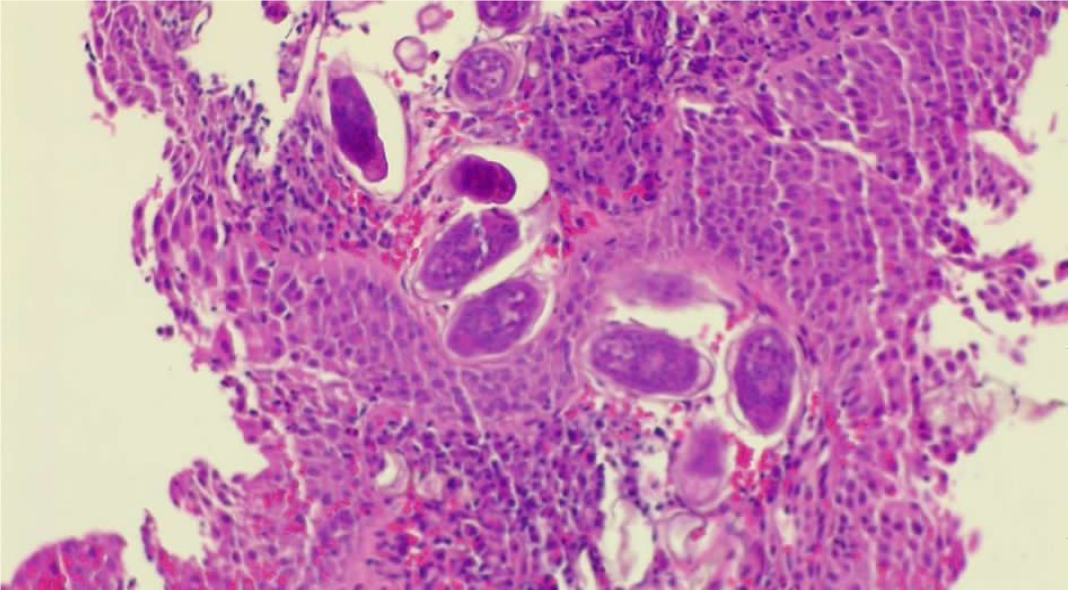

Solid oluşum olması üzerine üroloji ile konsülte edilen hastaya sistoskopi planlandı. Sistoskopide, mesane anterior superior duvarında yaklaşık 2×1 cm’lik papülonoduler lezyon görüldü (Resim 1-2). Lezyondan alınan biyopsi materyalinde lamina propriada parazitik infiltrasyon saptandı ve şiştozoma ile uyumlu olarak raporlandı (Resim 3). Eş zamanlı olarak mikrobiyoloji laboratuvarına gönderilen idrar örneğinde parazit yumurtaları tespit edildi (Resim 4). Hastaya praziquantel 2×40 mg/kg verildi. Bir ay sonra şikayetleri geçen hastanın kontrol idrar tetkikinde özellik yoktu. Sistoskopiyi kabul etmeyen hasta ülkesine döneceği için tekrar kontrole gelmedi.

En önemli tanı yöntemlerinde birisi USG’dir (4). Kesin tanı, idrar ve sistoskopi ile alınan biyopsi materyalinde parazit yumurtasının gösterilmesi ile konur (4,5,10). Olgumuzda da üriner USG sonrası yapılan sistoskopi ile elde edilen biyopsi materyali ve ışık mikroskobu ile değerlendirilen idrarda parazit yumurtalarının görülmesi ile tanı konuldu.